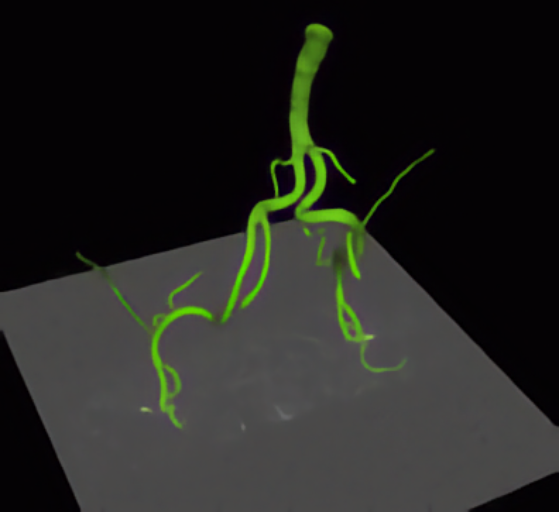

Model-based segmentation of vessels from 3D tomographic images. Quantification of the morphology based on 3D parametric intensity models.